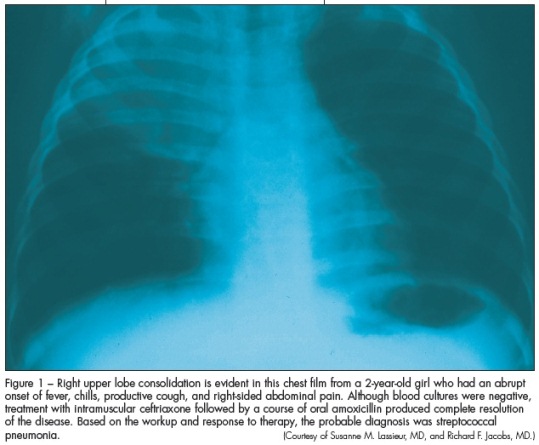

Anteroposterior and lateral chest radiographs help reveal areas of consolidation or interstitial disease in the ill patient (Figure 1). The pattern of abnormal findings on x-ray films provides a clue to the possible causative agent. Bacteria (S pneumoniae) are more likely to produce a lobar pattern and viral or atypical pathogens are more likely to produce an interstitial pattern. These radiographic descriptions are not absolute: bacterial and viral pathogens can produce various patterns of radiographic findings.

Occasionally we have seen patients whose radiographic features lagged behind the clinical presentation. Dehydration may affect the radiographic results. Hash and associates17 described an association between improved hydration and worsening of chest film findings in adults with clinical pneumonia. A patient may have a normal initial chest radiograph, but--after hydration is improved--an infiltrate may become evident on a subsequent film.17

During outpatient treatment, order follow-up chest radiographs when you suspect a complication such as pleural effusion or empyema, evidenced by chest pain, failure to respond to antibiotics, recurrence of fever, and worsening respiratory tract signs. Upright and lateral decubitus radiographs also may be necessary in this setting. After a patient completes therapy for uncomplicated pneumonia, repeated chest radiographs are not necessary; if they are obtained, however, be aware that initial radiographic abnormalities may take 6 or more weeks to resolve.